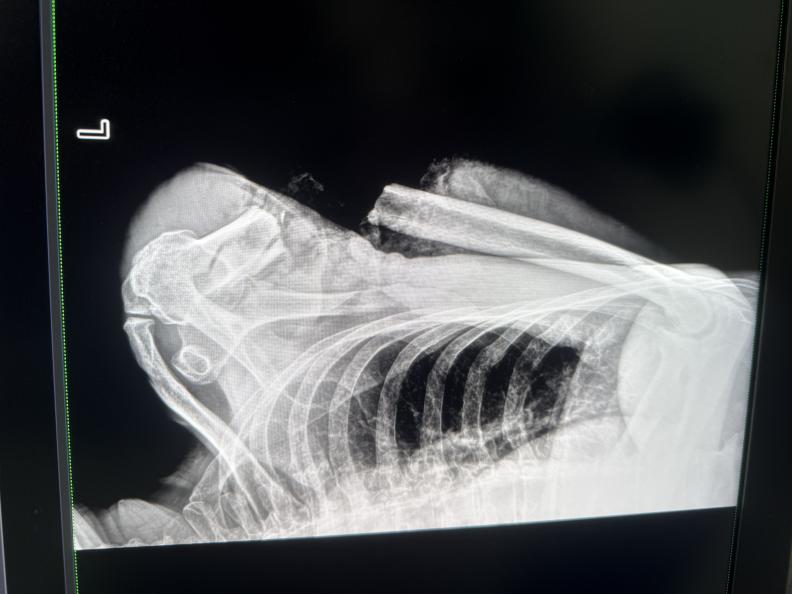

CT图像下冉文海断臂情况非常严峻。张晓锐供图

“左上臂已经完全离断,上臂上段呈环形开放性伤口,仅仅部分皮肤、肌肉相连,重要血管神经毁损长度达8厘米,污染物深入肌理,这比两年前病例更凶险的高位离断。”手术医师张晓锐回忆,团队果断启用“创伤优先分级救治系统”,在患者仍处于休克状态时,已同步完成离断肢体低温处理、三维CT血管成像和手术方案制定。